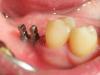

Andex Опубликовано 20 октября, 2012 Поделиться Опубликовано 20 октября, 2012 (изменено) В поддержании темы про применение мини-имплантов, хотел бы поделиться своим опытом. Прошу заранее прощения за качество фотографий - когда все в одном лице и врач и ассистент и медсестра и фотограф - тяжело сделать качественнее. Буду благодарен за конструктивные замечания и советы. 1) Имплантация 31 зуба. Ширина кости в медиодистальном размере- 2,8 мм, в вестибулооральном - 2,7. Имплант d 1.8 - L 13. Ниже файлы по порядку - оптг, прицельный рентген и живое фото 2) Имплантация 24 зуба. Имплант d 2.4 - L 10. Кости хватило бы и под двухэтапный. Файлы по порядку - живое фото, снимок с физиографа в перевернутом виде(так датчик развернулся) 3) Имплантация 46 зуба на двух мини-имплантах d 2.2 - L10. Восьмой удалять пациента не дался, поэтому начали лечение хотя бы с восстановления 46 зуба. Файлы - оптг, прицельный рентген, живое фото, рабочая модель, вид внутренней части коронки. Изменено 20 октября, 2012 пользователем Andex Ссылка на комментарий